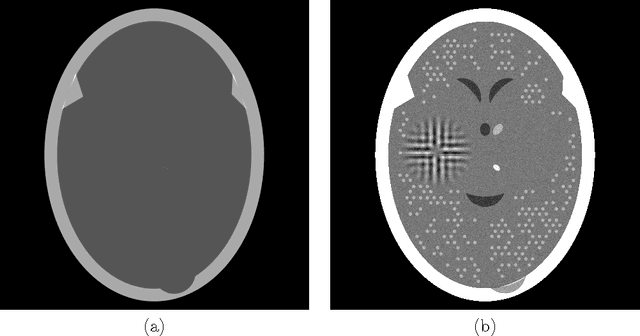

To reduce the x-ray dose in computerized tomography (CT), many constrained optimization approaches have been proposed aiming at minimizing a regularizing function that measures lack of consistency with some prior knowledge about the object that is being imaged, subject to a (predetermined) level of consistency with the detected attenuation of x-rays. Proponents of the shearlet transform in the regularizing function claim that the reconstructions so obtained are better than those produced using TV for texture preservation (but may be worse for noise reduction). In this paper we report results related to this claim. In our reported experiments using simulated CT data collection of the head, reconstructions whose shearlet transform has a small $\ell_1$-norm are not more efficacious than reconstructions that have a small TV value. Our experiments for making such comparisons use the recently-developed superiorization methodology for both regularizing functions. Superiorization is an automated procedure for turning an iterative algorithm for producing images that satisfy a primary criterion (such as consistency with the observed measurements) into its superiorized version that will produce results that, according to the primary criterion are as good as those produced by the original algorithm, but in addition are superior to them according to a secondary (regularizing) criterion. The method presented for superiorization involving the $\ell_1$-norm of the shearlet transform is novel and is quite general: It can be used for any regularizing function that is defined as the $\ell_1$-norm of a transform specified by the application of a matrix. Because in the previous literature the split Bregman algorithm is used for similar purposes, a section is included comparing the results of the superiorization algorithm with the split Bregman algorithm.